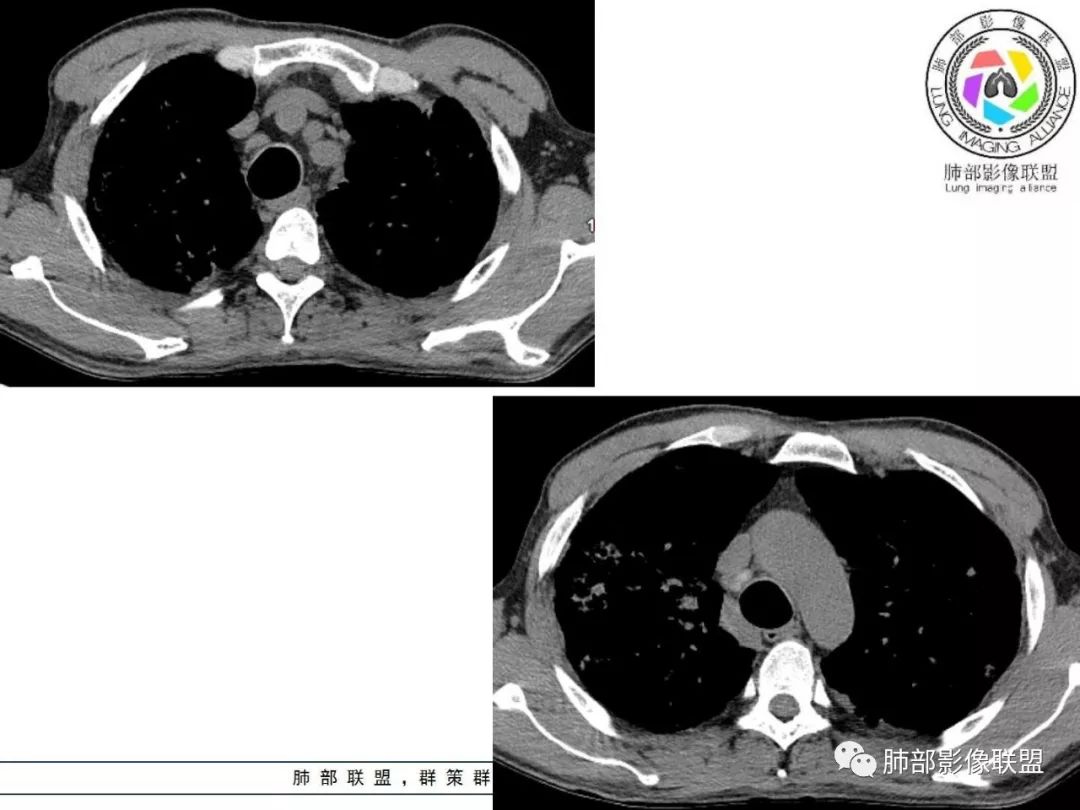

胸部CT:两肺弥漫病灶,磨玻璃影,少许实变,部分累及胸膜,磨玻璃区可见囊?少许胸腔积液,两肺可见结节,支气管血管束增粗,小叶间隔增厚,支气管走形有扭曲扩张,可见纤维化。气肿、大泡。考虑:感染性病变,PCP?查下HIV,CD4,G等。鉴别结核、结缔组织病肺浸润。

临床看,首先考虑感染性病变,特异性感染可能大,病毒直接pass掉,真菌和结核选一个。基础病变是肺气肿,不能看成蜂窝征。肺门淋巴结有钙化趋势,午后低热。心包胸腔都有少量积液。病变渗出和实变并存。结核

从内科的角度一点不意外,而且病史采集很到位,午后低热,同时出现心包和胸腔积液,常见病中,最可能是结核和转移。前面说过,其他一些征象也支持结核。

弥漫性间质疾病,还伴心包,胸腔积液的,肺水肿也有可能,但临床不符,没有胸闷气急。

这个病例气管横径=同侧脊柱横径,需考虑气管支气管巨大症?

2. 肺气肿背景(小叶中心性肺气肿);双肺多发病灶整体沿血管支气管束及胸膜下分布,以上叶及下叶背段分布为主,有实变及GGO,边界清楚,有树芽,小叶间隔及中央间质增厚,叶间裂见到多发结节,部分支气管不规则牵拉扩张,提示病灶纤维化明显,结合临床病史,考虑病灶为间质性感染,肺门及纵隔内有钙化淋巴结,小叶间隔结节,考虑淋巴道增值性疾病可能,综合常规要怀疑间质性肺结核。